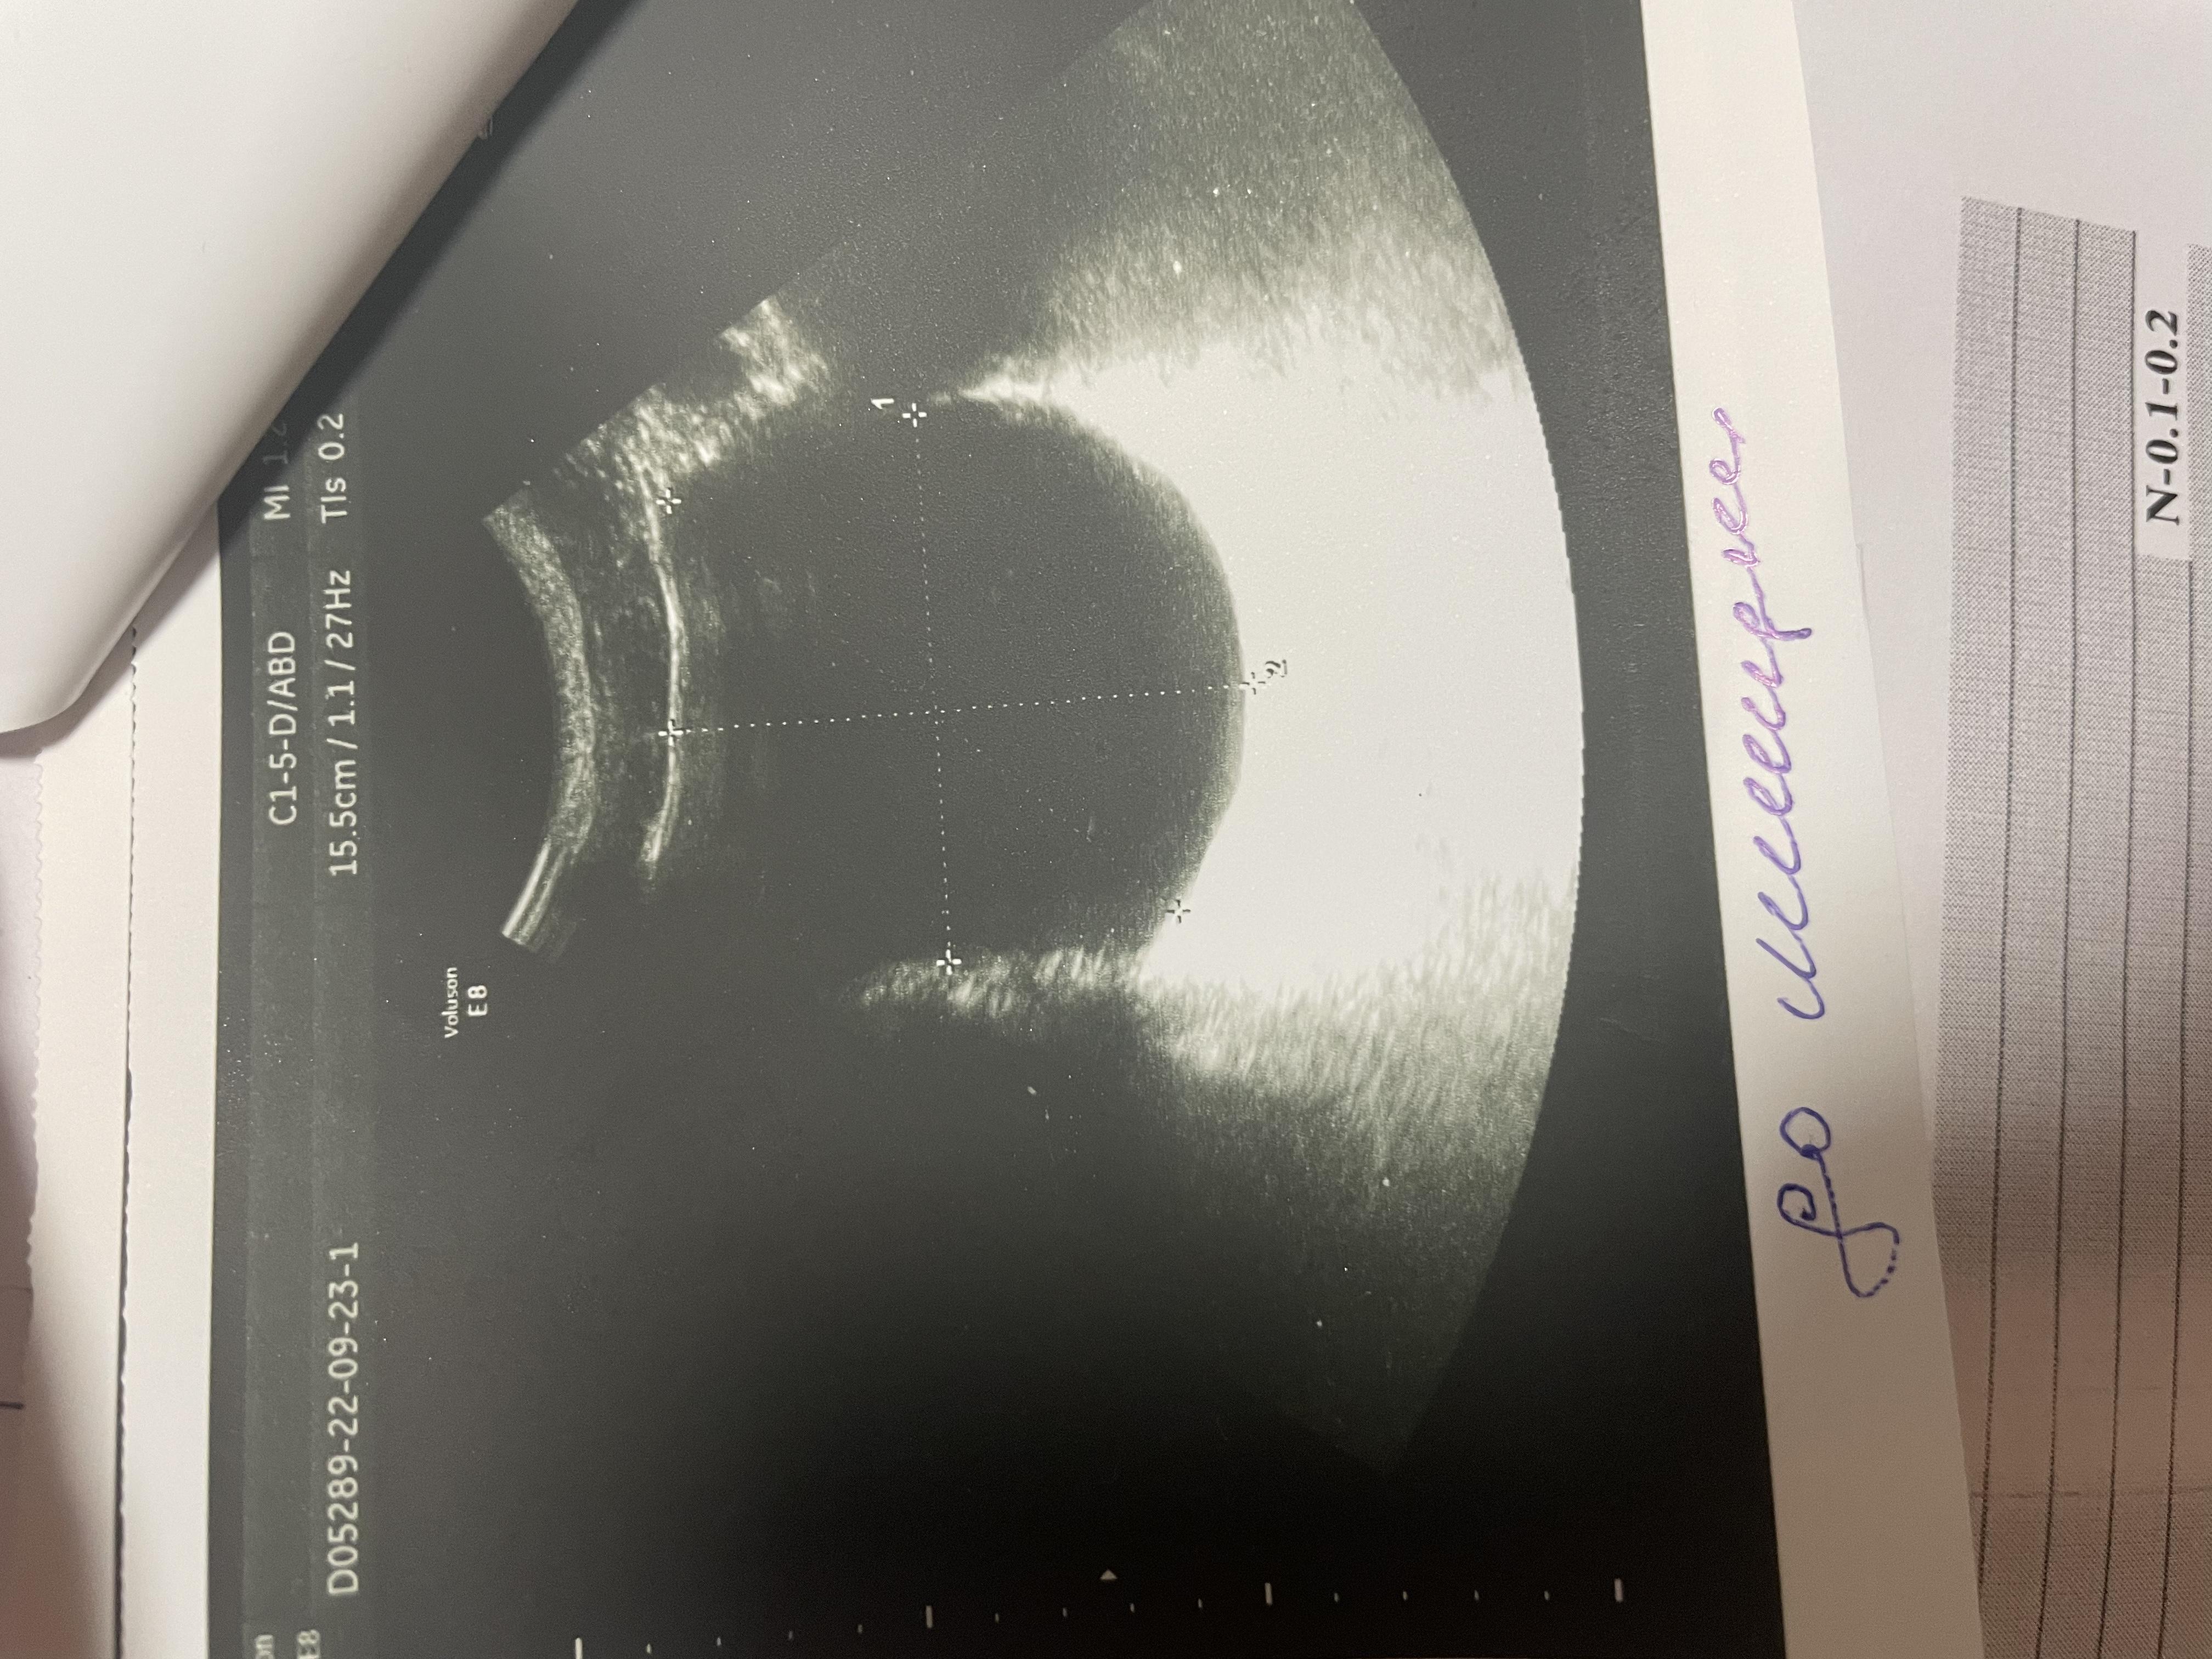

Здравствуйте, болят яички 1.5 года. 6 месяцев режет при мочеиспускании, боли в копчике (начинается с копчика, в течение дня усиливаются, поднимаются выше боли). Может ли это быть из-за мочевого пузыря? Фото прикрепил, там есть образование некое. Бак посев мочи отриц, эр, лейк. в норме, зппп отриц, в секрете простаты клебсиела, кровь в норме, млча в норма. Мрт поясницы делал, невролог сказал, что боли точно не из-за невролгии.

Добрый день! Вам нужно выполнить МРТ малого таза - там будет видно образование в стенке мочевого пузыря (если оно действительно есть). После этого надо обратиться к онкоурологу для интерпретации результатов МРТ и решения вопроса о дальнейшей тактике. Удачи.